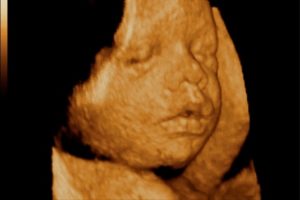

Если снимки выполняют посредством 3D УЗИ, то на фотографии можно рассмотреть радужную оболочку глаза.

Что интересно — на сроке 31 неделя беременности при УЗИ на фото и видео уже можно достаточно подробно рассмотреть черты лица ребенка.

Конечно, цвет глаз еще не рассмотреть (хотя радужная оболочка в этот период уже начинает приобретать свойства взрослого глаза и реагирует на яркий свет), но сейчас все более популярной становится технология 3D и 4D УЗИ, которая дает наибольшие возможности в визуализации плода.

В этот период беременности можно наблюдать в процессе УЗИ эмоциональную активность плода, а также рассмотреть первые движения ребенка, его способность сосать палец. После ультразвуковой диагностики мама получит симпатичное фото своего крохи.